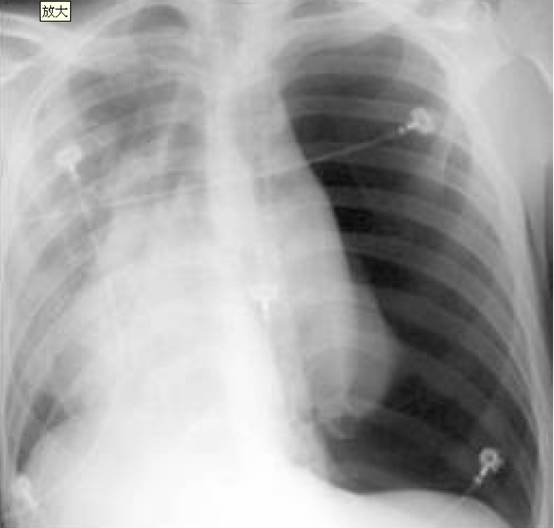

1. 20歲男性因“呼吸困難半小時”來診,伴有大汗、心悸。胸片如圖

考慮診斷:

A. 右側肺炎

B. 左側肺栓塞

C. 左側氣胸

D. 右側肺不張

答案:1. C; 2. B; 3. C; 4.B